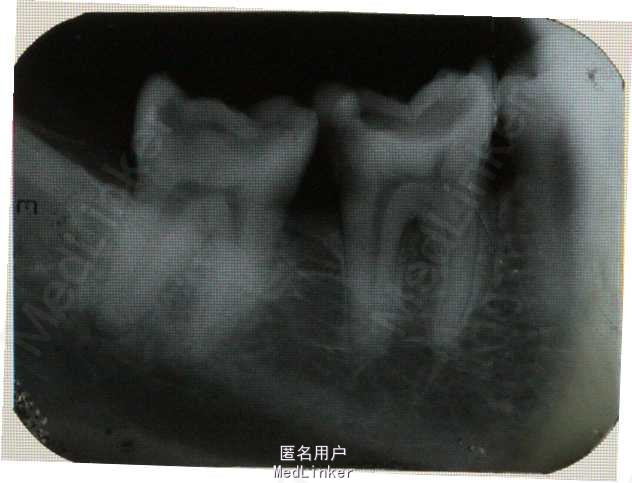

患者,男,48岁。左下后牙疼痛3天。

口内检查:见36,37牙冠大面积龋坏,进髓。扣++,冷+,探+。无明显松动,颊侧无瘘管。牙周状况一般。 牙片示:36,37深龋近髓,37远中根尖有明显暗影。

诊断:36慢性牙髓炎;37慢性根尖周炎。 处理:36,37根管治疗+纤维桩+冠修复